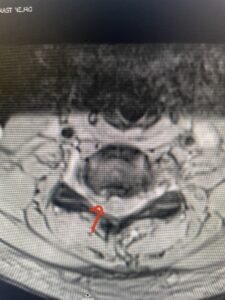

Fig: 2b Axial T2-weighted cervical MRI demonstrating spinal cord compression from C4-5 herniated disc (red arrow)

This 47-year-old male who four months prior was lifting weights developed sharp pain in his neck. After that he developed progressive numbness in his arms, neck pain and headache. He said that the right arm was worse than the left. On examination the patient had long tract weakness on the right side which included his triceps, finger extensors, hip flexors, and dorsiflexors. The patient did not have hyperreflexia. MRI (Fig. 2) demonstrated a massive, extruded disc herniation with severe cord compression. The patient because of progressive myelopathy and spinal cord compression was indicated for anterior cervical discectomy and fusion at C4-5 (Fig. 3). Patient had significant improvement of weakness and numbness post operatively.